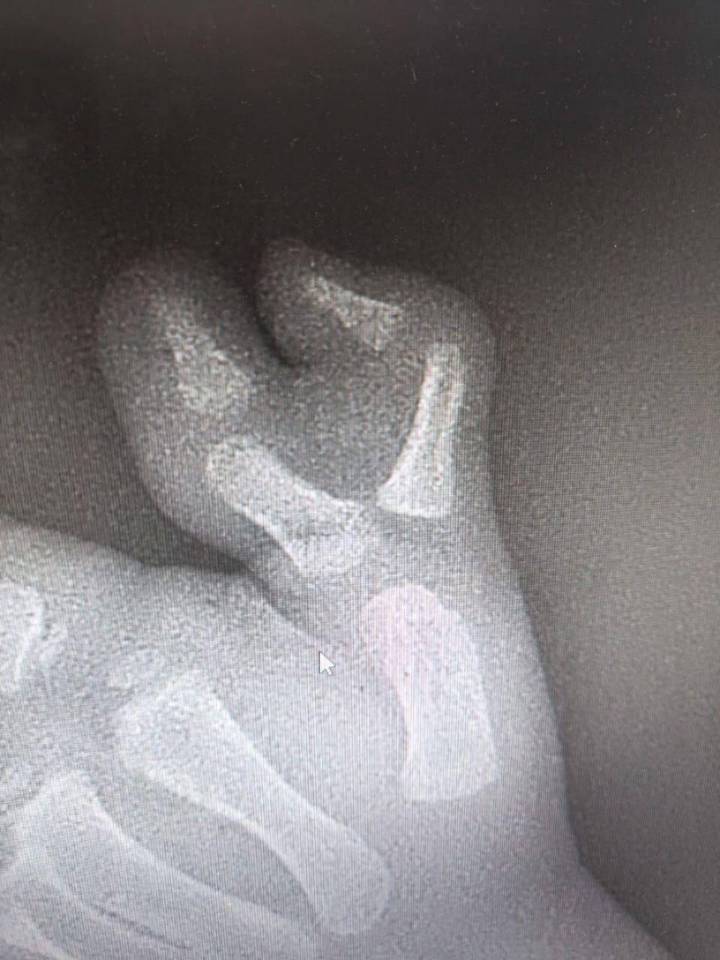

Подмосковные врачи удалили ребенку шестой палец на руке

Врачи Московской областной детской клинической травматолого-ортопедической больницы (МОДКТОБ) удалили трехлетнему мальчику шестой палец на руке. Об этом в четверг, 27 ноября, сообщили в пресс-службе министерства здравоохранения региона.

— У маленького пациента рос добавочный палец, вызывая как физические, так и психологические трудности. После всех необходимых диагностических мероприятий ребенку провели операцию, — сказано в сообщении.

Как уточнили в пресс-службе, операция прошла успешно. На данный момент ребенка уже выписали из стационара на амбулаторное лечение по месту жительства. После полного восстановления мальчика ждет повторная операция для удаления металлоконструкции. Однако в дальнейшем функция кисти полностью восстановится, передает сайт Минздрава.

Подмосковные врачи удалили ребенку шестой палец на руке Подмосковные врачи удалили ребенку шестой палец на руке / Фото: Пресс-служба министерства здравоохранения Московской области

До этого хирурги Филатовской детской больницы прооперировали пятилетнего мальчика с полидактилией: у него на обеих руках были лишние пальцы. Миша появился на свет с врожденной аномалией, при которой на руках развиваются лишние пальцы. Врачи Филатовской больницы провели операцию, удалив лишние фрагменты пальцев и восстановив форму большого пальца.